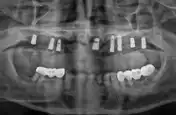

전

엄마 임플란트 해드려야해서 모시고 갔는데 왠만한 치과치료는 다 가능하네요~ 동네에 큰 치과병원이 있어서 든든해요 원래 치아가 약하셔서 이번에 효도할겸 임플란트 해드렸는데 자세하게 검사 해주시고 잇몸 위치, 뼈상태부터 어떤 치료를 왜 해야하는지 까지 설명을 해주셔서 좋았어요~ 아빠도 의사선생님 기술이 좋은거 같다며 ㅎㅎ 엄마 부러워 하셔서 예약 잡았어요